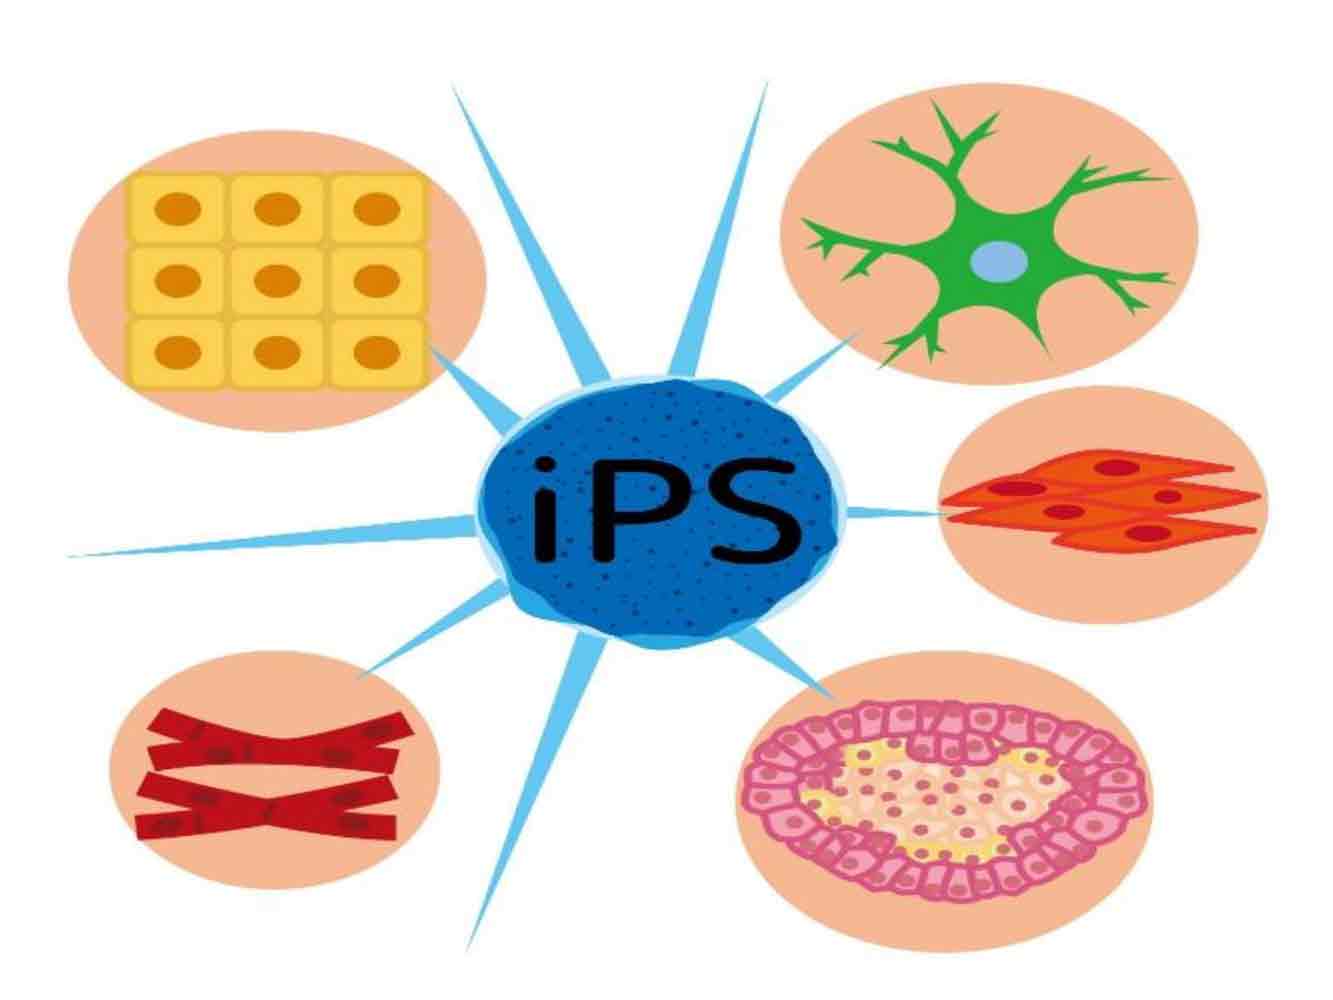

幹細胞注射

幹細胞注射とは、自身の脂肪組織や骨髄から幹細胞を搾取し、それを股関節に注入することで、軟骨や骨の再生を促します。再生医療に関しては、現在の所日本では保険適応外となっており、治療費がかなり高額になってしまうのが難点です。